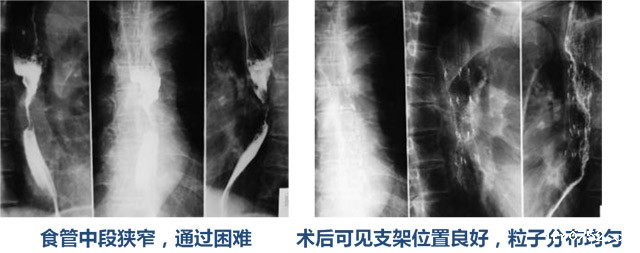

病例3:食管癌行125I粒子支架置入术,食管中段狭窄,通过困难 术后可见支架位置良好,粒子分布均匀。